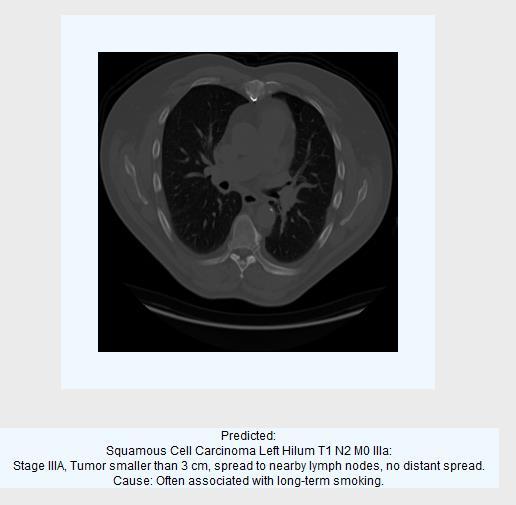

2.3.3Classification output images:

Fig7: Predictedascancercell-SquamousCellCarcinoma